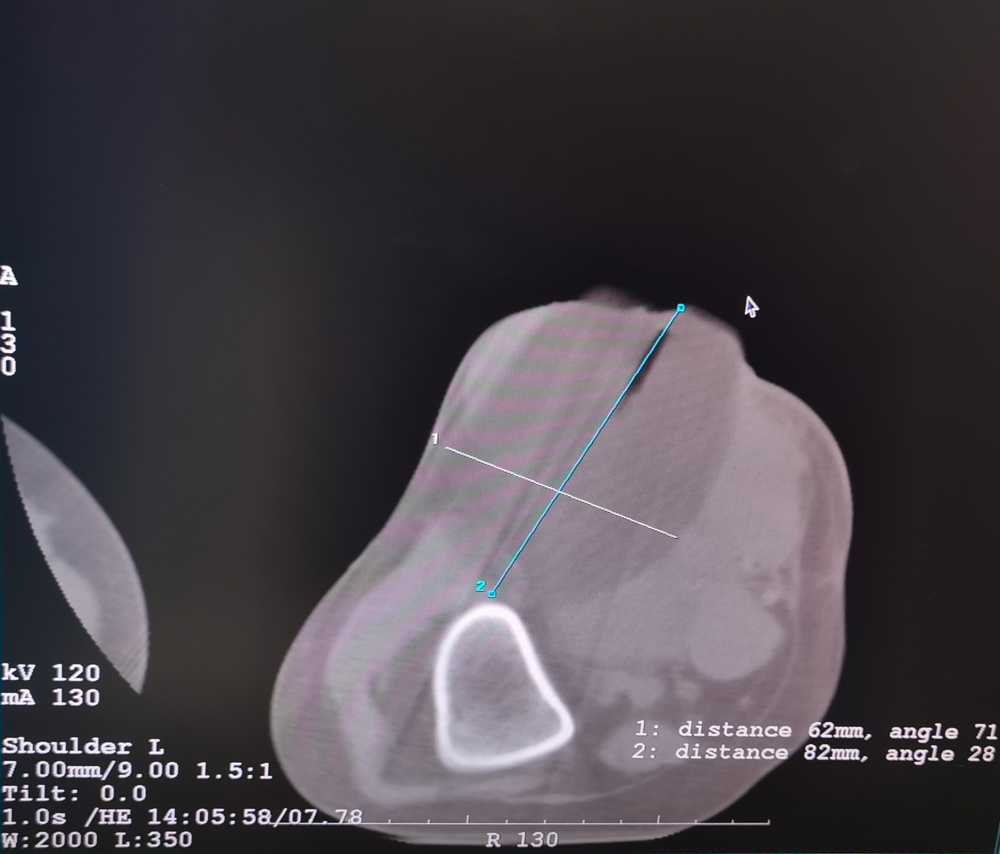

女,56歲,肺轉移瘤,骶骨、左側肋骨各一轉移灶,病灶大小均為5cm。骶骨轉移灶、肋骨轉移灶各進行2個凍融循環(huán)。患者術后狀況良好。

女,42歲,復發(fā)性脂肪瘤,病灶位于右側膝關節(jié),直徑大小13cm。采用雙針方案,共進行6個凍融循環(huán),最大冰球直徑達8.2cm,術中多方位治療全面覆蓋病灶范圍。患者術后狀況良好。